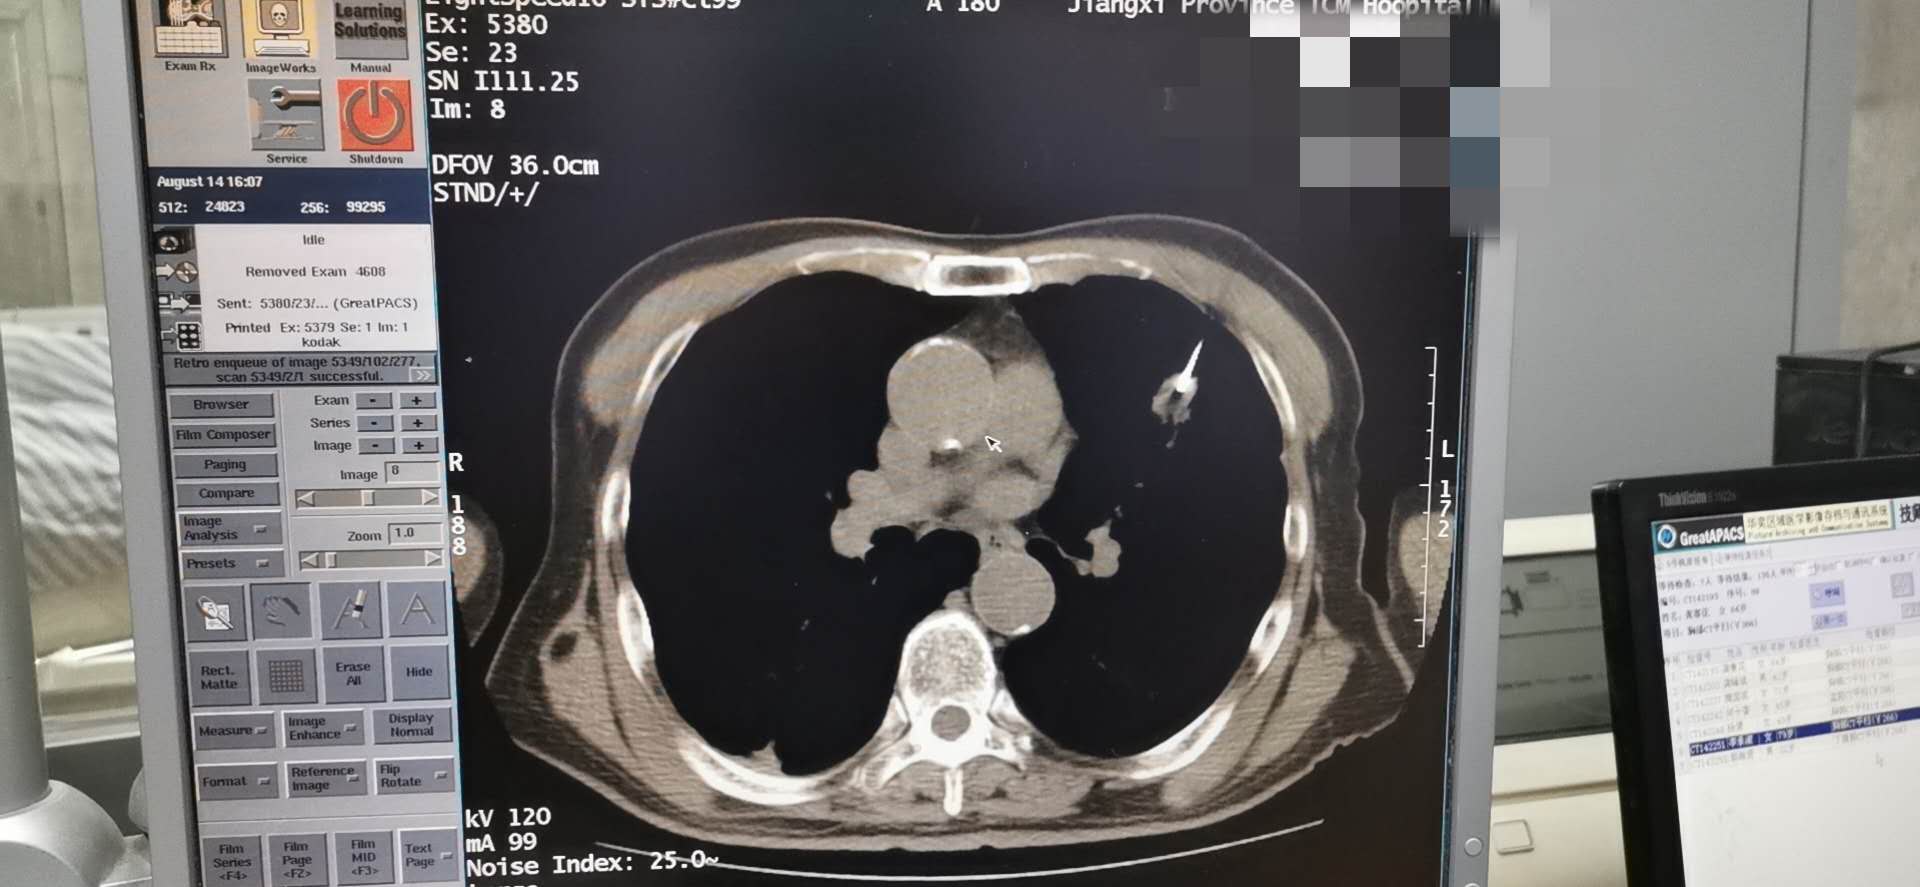

我院肿瘤科8.14于CT引导下完成肺穿刺术

为明确诊断及指导下一步治疗方案。我科洪禹霖副主任医师、张峰浩医师、吁佳副主任护师精诚配合下于8.14日成功完成一例肺小结节穿刺术,术后无明显气胸及出血并发症、患者安返病房。